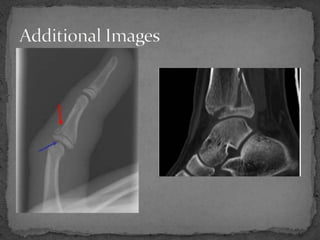

An 11-year-old male presented to the emergency department after being kicked by a cow, unable to bear weight on his right leg and experiencing excruciating pain. Examination revealed swelling and bruising around the right ankle with pain on movement. X-rays showed a fracture extending from the metaphysis through the epiphysis, classified as a Salter-Harris Type IV injury. This type of injury crosses the physis and involves both the epiphysis and metaphysis, is associated with a worse prognosis than other types, and may affect growth even with perfect reduction. Orthopedic consultation was recommended for possible open reduction and internal fixation if any displacement was present.